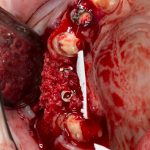

При вертикальной остеотомии очень удобно использовать длинные винты. Так, как указано на схеме.

Кроме того, с помощью винтов можно «прецизионно» зафиксировать костный фрагмент, передвигая его как на домкрате: